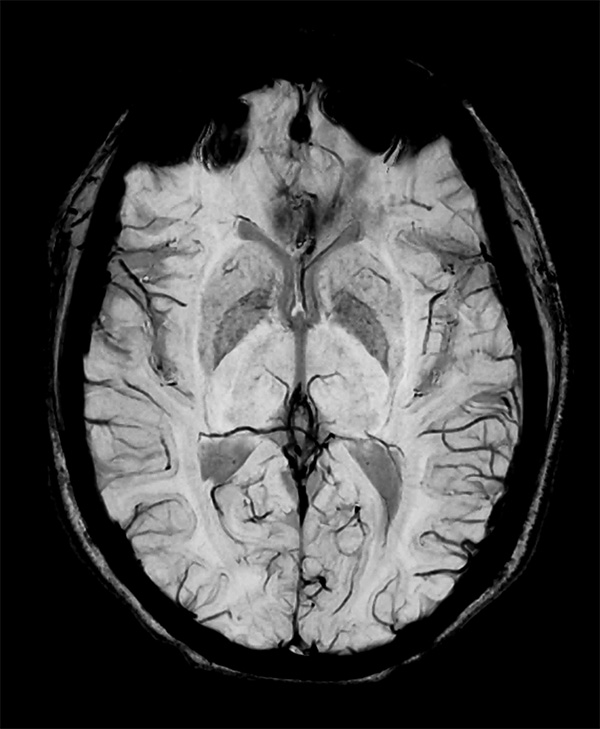

Comprehensive Brain imaging at 3.0T

• Clinical Application